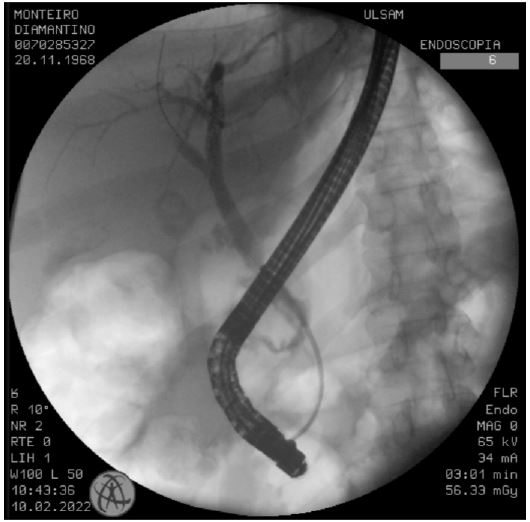

Three days later, the patient was extubated and transferred to a hospital closer to his residence. Upon arrival, clinical deterioration occurred, characterized by cardiovascular and neurological dysfunction, necessitating reintubation. The previously purulent abdominal drainage had changed to enteric characteristics, prompting a new CT scan, which indicated a multiloculated retroperitoneal collection extending from the right flank to the pelvis, suggestive of bowel perforation (Figure 1). The patient was taken for laparotomy, during which a large infected retroperitoneal hematoma was identified and extensively debrided and bowel perforation was ruled out. Two drains were placed in the right flank and peri-hepatic space. The surgery proceeded without complications. However, on the first postoperative day, a high output of biliary content was noted in the abdominal drains. Bilirubin analysis of the drain’s contents confirmed the presence of biliary drainage.

Figure 1: Abdominopelvic CT scan previous to the exploratory laparotomy: Evidence of a multiloculated retroperitoneal collection (arrow) extending from the right flank till the pelvis with a heterogeneous aspect.